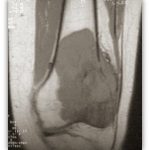

Η Μυοσκελετική Ογκολογία ασχολείται με την διάγνωση και την αντιμετώπιση των καλοήθων και κακοήθων όγκων των οστών και των μαλακών μορίων όταν εντοπίζονται στα άκρα.

Η απεικόνιση των βλαβών πρέπει να κατευθύνεται από τον Ορθοπαιδικό Χειρουργό και ακολουθεί μία συγκεκριμένη μεθοδολογία.